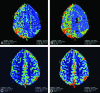

Results: Among 1850 MR imaging studies, 20 (1.08%) patients were found to have acute migrainous aura. Hypoperfusion was found in 14/20 patients (70%) with delayed rMTT and TTP, decreased rCBF, and minimal decrease in rCBV. In contrast to the typical pattern in stroke, perfusion abnormalities were not limited to a single vascular territory but extended to >1. Bilateral hypoperfusion was seen in 3/14 cases. In 11/14 cases, hypoperfusion with a posterior predominance was found. TTP and rMTT were the best maps to depict perfusion changes at visual assessment, but also rCBF maps demonstrated significant hypoperfusion in quantitative analysis. In all patients, clinical and imaging follow-up findings were negative for stroke.